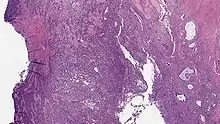

Undifferentiated uterine sarcoma

Undifferentiated uterine sarcoma, or undifferentiated (high-grade) endometrial stromal sarcoma, does not resemble normal endometrial stroma and behaves much more aggressively, frequently metastasizing. The differential includes leukemia, lymphoma, high-grade carcinoma, carcinosarcoma, and differentiated pure sarcomas.

Microscopy

- Monotonous ovoid cells to spindly cells with minimal cytoplasm.

- Prominent arterioles. Angiolymphatic invasion common.

- Up to 10-15 mitotic figures per 10 HPF in most active areas.

- Tongue-like infiltration between muscle bundles of myometrium.

- May exhibit myxoid, epithelioid and fibrous change.

- May have foam cells or hyalinization in the stroma.